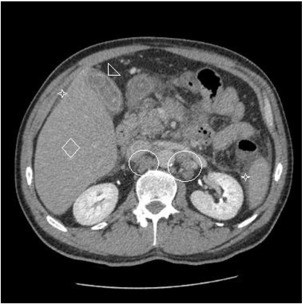

Спустя два месяца после достижения УВО, и, несмотря на то, что неоднократно документировалась полная ремиссия ДККЛ (ПЭТ КТ, гематологические показатели), в течение двух последующих лет наблюдения, пациент поступил в стационар с отчетливой болью в правом верхнем квадранте и ухудшением функций печени.

Визуально отмечалась желтизна кожных покровов и склер. КТ показала генерализованную лимфаденопатию, аномальное утолщение конечной подвздошной кишки, гепатоспленомегалию с выраженным асцитом (рис. 2).

Пункционная биопсия печени показала (рис. 3) обширную инфильтрацию ДККЛ в паренхиму печени (этап IV Энн Арбор при рецидиве, IPS: высокий, R-IPS: низкий). На момент исследования профиль ДККЛ был таким же, как и при первичном обращении (CD20+, PAX-5+, CD3-, CD30-). Летальный исход пациента был обусловлен развитием печеночной недостаточности незадолго до получения химиотерапии.